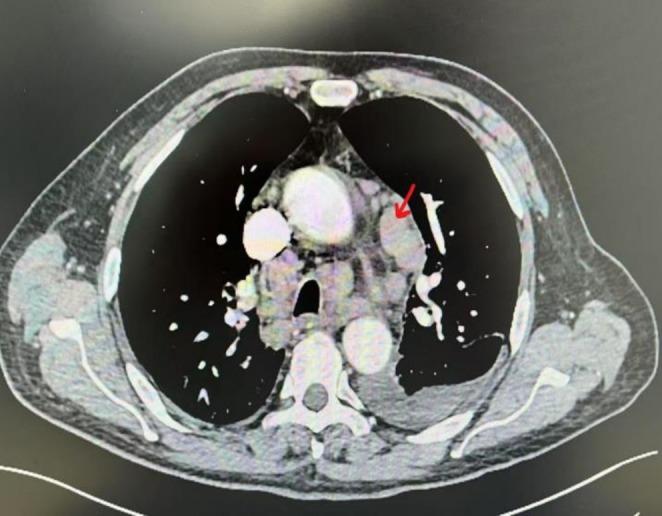

Rosai-Dorfman disease (RDD), a rare form of histiocytosis, predominantly affects young individuals. Clinically categorized into nodal and extranodal subtypes, the disease primarily involves systemic lymph nodes with possible involvement of other organs. This variability in organ involvement leads to diverse clinical manifestations and nonspecific imaging findings, contributing to frequent diagnostic challenges and misdiagnosis. Histopathologically, the characteristic cells demonstrate S100+, CD68+, and CD1a-negative immunophenotype. We present a rare geriatric case of RDD, which may enhance diagnostic awareness and clinical management of this condition. Further research is warranted to advance our understanding of RDD pathogenesis and therapeutic strategies.